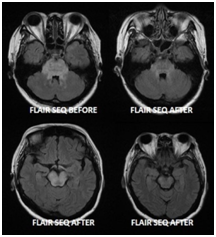

We present a 16-year-old female presented, one week postpartum with seizures. She had normal blood pressure throughout her pregnancy and afterword's had normal pregnancy until she had a seizure. Her neuroimaging showed features of high signal lesion within cortex and subcortical lesion of both parietal and occipital lobes with associated gyral swelling, with no associated gyral restriction. Her neuroimaging showed features of PRES with resolution on repeat scan, see case and Figure 1.

Figure 1 Image quality degraded by dental braces induced artefacts. There are high signal lesions within the cortex and subcortical region of both parietal and occipital lobes with associated gyral swelling. No associated restricted diffusion. The appearances favor PRES. Follow up images after treatment revealed significant improvement.

A 17-year-old female presented, with three generalized tonic clonic seizure, with preceding abdominal pain (non-surgical) for three days with vomiting. She had autonomic dysfunction with heart rate ranging from 63-120 beats per minute, with blood pressure ranging from systolic 174-110 and diastolic from 120-80mmHg. Her Urinary porphobilinogen and aminolevulinic acid were markedly increased consistent with acute intermittent porphyria and her high signal lesions within the cortex and subcortical region of both hemisphere with associated gyral swelling. No associated restricted diffusion. Her neuroimaging showed features of PRES and favors PRES with resolution on repeat scan. Follow up images after treatment revealed significant improvement, see case and Figure 2.

Figure 2 There are high signal lesions within the cortex and subcortical region of both hemispheres with associated gyral swelling. No associated restricted diffusion. The appearances favor PRES. Follow up images after treatment revealed significant improvement.